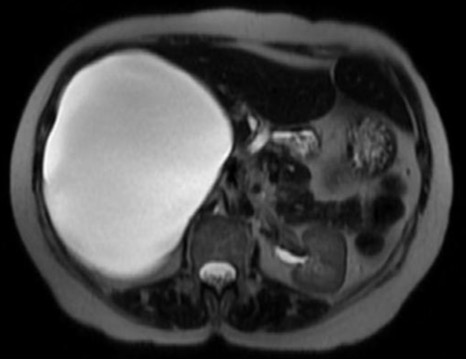

Aspetto RM

- Alterazione focale ben circoscritta, ipointensa in T1, iperintensa in T2 (isointensa al liquor), priva di enhancement post-contrastografico.

- Nelle sequenze colangiografiche non si riconosce una comunicazione con l’albero biliare.

- La cisti epatica a contenuto proteinaceo ha segnale iperintenso in T1.

- Nel caso di emorragia intracistica, il segnale sarà eterogeneo sia nelle sequenze T1 che T2, spesso con un livello fluido-fluido.